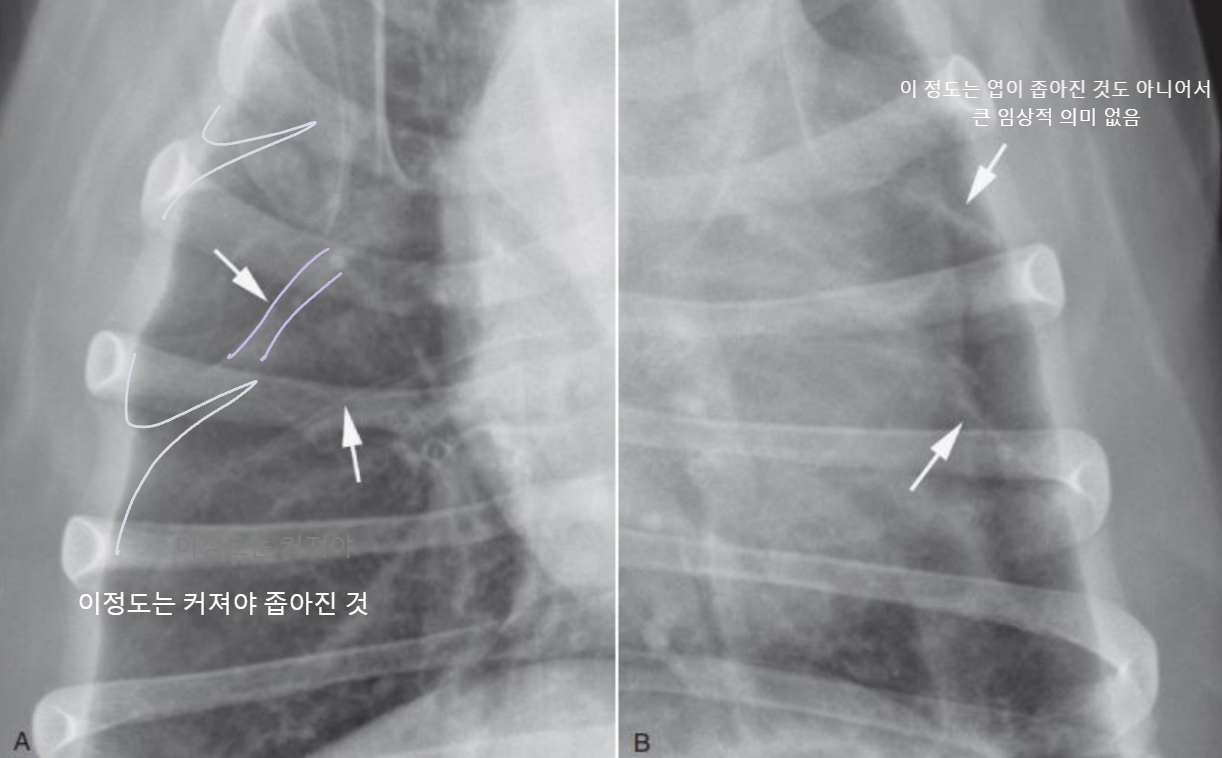

4. Pleural Space

| Pleural effusion (ํ์) | Pneumothorax (๊ธฐํ) | |

|---|---|---|

| ํ๊ฐ(pleural cavity)์ ๋ฌผ์ด ์ฐฌ ๊ฒ (ํ์ ์ฐจ๋ฉด โ ํ์์ข ) | ํ๊ฐ์ ๊ณต๊ธฐ๊ฐ ์ฐฌ ๊ฒ (ํ์ ์ฐจ๋ฉด โ ํ๊ธฐ์ข ) | |

| Radiographic signs interlobar fissure ๋๊ป๊ฒ ๊ด์ฐฐ๋๊ณ , ํ๋ฒฝ์ด ๋จ์ด์ ธ ๋๊ฐ ๊ฒ์ฒ๋ผ ๋ณด์ | Radiographic signs ์ฌ์ฅ์ด ๋ ์๊ณ , ํ๊ฐ ์ชผ๊ทธ๋ผ๋ฆ | |

| - Interlobar fissure widening - Lung retraction - Pleural wall thickening - Scallop sign - Cardiac effacement - Blunt angle | - Retraction of pleural surface - Collapsed lung (โ opacity ์ฆ๊ฐ) | |

![]() | ![]() | |

![]() ![]() | ![]() ![]() | |